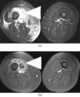

Soft tissues abscess

An abscess is a collection of pus that has built up within the tissue of the body. Signs and symptoms of abscesses include redness, pain, warmth, and swelling. [Source: Wikipedia ]